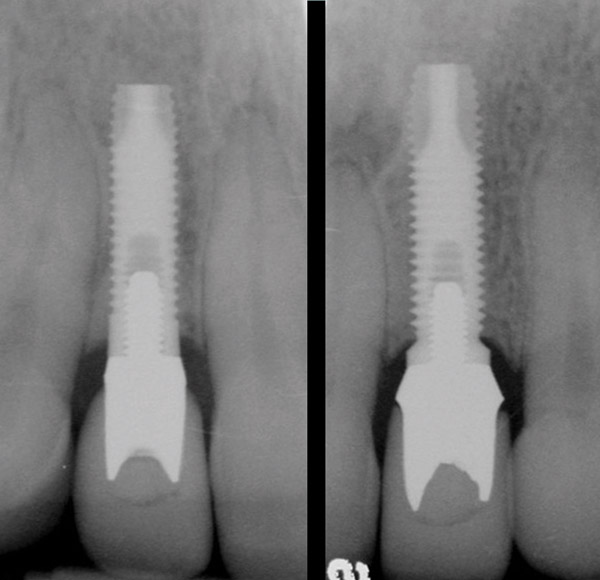

Figure 3  Periapical radiograph of implants in the Nos. 8 and 9 sites 3 years after placement. A bony peak was still present between the implants due to successful guided bone regeneration and favorable fixture spacing.

Figure 3

Figure 4  Final restoration of implants in the Nos. 8 and 9 sites 3 years after placement. Note the short central papilla regardless of the presence of bone. Restoration courtesy of Dr. Alan Goldberg.

Figure 4

Figure 5  A naturally low smile line hid the clinical “black triangle” from view.

Figure 5